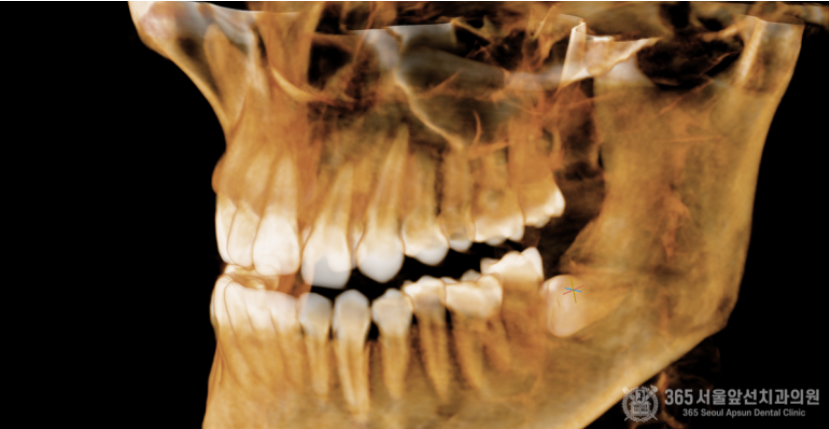

아래턱에 매복사랑니가 있는데, 집근처 동네치과에서 발치가 불가능하다고 대학병원에 가보라고 했어요. 오늘은 완전수평 매복 사랑니의 발치 증례를 소개해드리겠습니다. 집 근처 치과에 방문했다가 완전수평 매복사랑니 발치가 불가능하다는 판정을 받은 환자분께서 내원하셨습니다. 촬영일시 : 2024.05.15. 초진 엑스레이 사진입니다. 완전히 수평으로 매복되어 있으며, 신경관과 뿌리가 겹쳐져 있는 양상이 관찰됩니다. 환자분께선 발치가 불가능할까봐 걱정이 많으셨으나 걱정하지말라고 안심시켜드리고 매복 사랑니 발치를 진행했습니다 ㅎㅎ 촬영일시 : 2024.05.15. 3차원 CT 영상입니다. 뼈 속에 완전히 파묻힌 사랑니를 볼 수 있습니다. 촬영일시 : 2024.05.15. 신경관과 뿌리가 겹쳐져 있는 양상도 관찰됩니다. 조심스럽고 안전한 발치가 필수적이겠습니다. 촬영일시 : 2024.05.15. 발치 후 엑스레이 사진입니다. 발치에 소요된 시간은 총 10분으로 정확하고 빠르게 발치해드렸습니다. 빠르고 정확한 진료를 추구하는 강동우 대표원장이었습니다. 365서울앞선치과의원은 365일 늘 가까운 서울대학교 치과병원을 지향합니다! [ 치료기간: 2024년 5월15일 ] ※ 365서울앞선치과의원의 모든 포스팅은 각 진료과 의료진이 직접 작성합니다. 365서울앞선치과의원 블로그의 임상 케이스 게시물은 환자분께 의학적으로 정확하고 상세한 정보를 드리기 위해 각 진료과 의료진이 직접 작성하며, 모든 증례 사진은 본원 의료진이 직접 시술한 증례를 촬영한 것으로, 의료법 제23조, 제56조에 의거하며 환자분의 동의를 얻어 포스팅에 사용하였습니다. 또한 해당 케이스는 본 환자분의 치료 결과이며, 환자 상태에 따라 치료의 결과는 달라질 수 있습니다. |